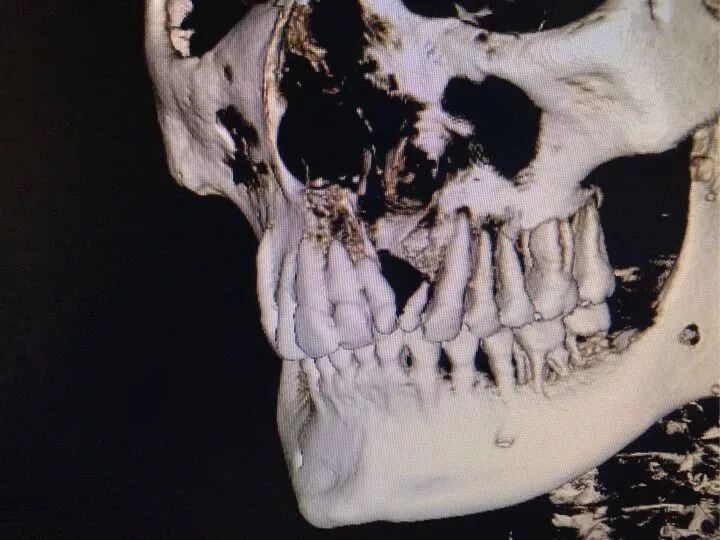

CBCT(锥形束CT)

CBCT是个三维立体的诊断,现在的软件也可以更为直观的重建软硬组织

如应用在牙齿正畸上,对于二维的无法判断比邻关系的牙齿,最好拍个CT来明确位置关系,也可以拍摄CBCT来直观的判断牙根被骨壁包绕的情况,在大量内收的情况下来判断是否有骨开窗的风险(牙移动过快,角度变化大,牙根从骨头处破窗而出)所以角度很大的牙齿,大量内收,拍摄CT是很常规的了!

曲断发现的埋伏牙,牙根内外吸收,根折一般都会拍摄CT。

门牙处没有骨头,做正畸牙肯定会掉